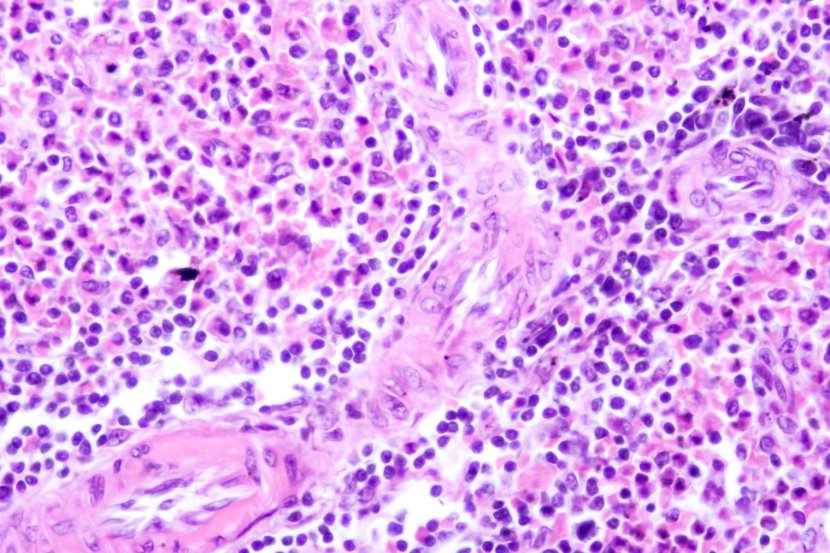

PEComa se razvija iz specifičnih ćelija koje se u normalnim uslovima ne nalaze u telu. Njihovo ime – „perivaskularne epiteloidne ćelije” – potiče od toga kako izgledaju pod mikroskopom. Još uvek nije u potpunosti jasno odakle ove ćelije potiču.

Pod mikroskopom, PEComa izgleda kao skup epiteloidnih ćelija raspoređenih oko krvnih sudova. Uglavnom sadrže proteine koji su slični onima u ćelijama koje proizvode melanin i u glatkim mišićima.